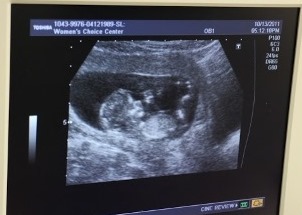

Następnie ks. Peter West i Chris Morales odwiedzili ośrodek pomocy kobietom w ciąży Women's Choice Center. Zgodnie ze strategią ruchu pro-life ośrodki te są zawsze położone w bezpośrednim sąsiedztwie placówek aborcyjnych Planned Parenthood. Ich celem jest niesienie bezpośredniej pomocy zestresowanym kobietom w ciąży i proponowanie im alternatywnych, pozytywnych rozwiązań. Tutaj centrum pro-life znajduje się dosłownie po drugiej stronie ulicy, naprzeciwko placówki oferującej aborcję.